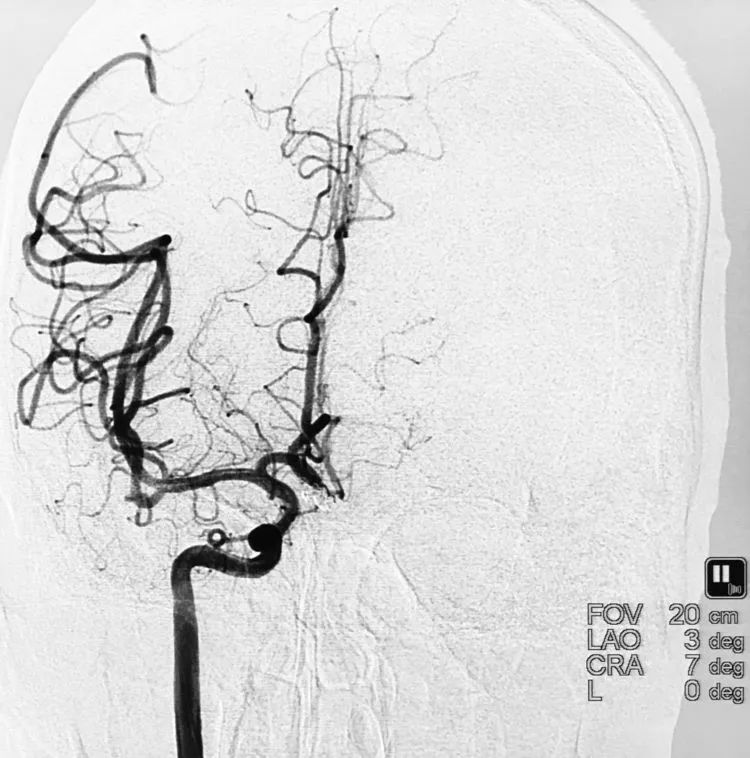

例3,女,57岁,因体检行头部MRA发现颅内动脉瘤2天于2011年10月26日收入院。高血压病史5年。查体无明显阳性体征。于11月2日行DSA+介入治疗。术前左颈内动脉造影显示左侧颈内动脉眼动脉段动脉瘤,呈牛角形分叶;三维重建测量,瘤颈宽9.0 mm,大分叶7.9 mm×7.8 mm,小分叶3.7 mm×5.7 mm:

计划支架结合双微导管技术栓塞。左颈内动脉工作位(右斜35°)路图下,经8F导引导管送入三套微导管系统,PROWLER SELECT PLUS支架导管在Traxcess-14微导丝引导下进入左大脑中动脉;第一根Echelon-10微导管(甲管,头端塑成C形)送入动脉瘤近心端的小分叶;第二根Echelon-10微导管(乙管,45°预塑形)送入远心端的大分叶:

术后左颈内动脉工作位造影显示动脉瘤完全栓塞: